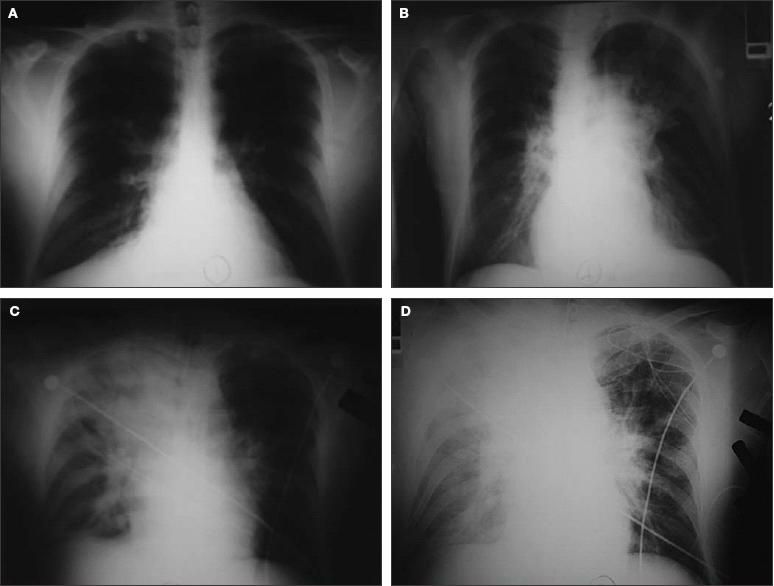

Four reviews have described the classic signs and symptoms of inhalational anthrax (Table).5,16,75,76 The most common symptoms at presentation include chills or fever (67%), malaise (64%), cough (62%), and dyspnea (52%). Most patients at presentation were febrile (66%) or tachycardic (66%). Of the 26 patients who had a chest radiograph, all had abnormalities, including pleural effusions (69%) and widened mediastinum (54%) (Figure 2). However, because chest radiographs were obtained from only 32% of all reported cases of inhalational anthrax, the lack of a radiographic abnormality should not exclude the diagnosis.5

Figure 2 – These chest radiographs are from a 49-year-old postal worker who had untreated inhalational anthrax. He presented to an emergency department complaining of myalgia, fatigue, nausea, stomach pain, and light-headedness of 3 days' duration. A chest radiograph showed a right suprahilar density (A). Unfortunately, the patient was sent home without antibiotics, but returned 24 hours later complaining of syncope, diaphoresis, and ongoing GI complaints. His chest radiograph showed increasing perihilar/infrahilar densities (B). He was triaged inappropriately and within 3 hours had septic shock complicated by hypoxemic, hypercapnic respiratory failure requiring mechanical ventilation. His radiograph showed a new right upper lobe infiltrate (C). Despite antibiotics, refractory septic shock and worsening respiratory failure developed, with radiographic evidence of increasing right upper lobe infiltrate and new bilateral pleural effusions (D). The patient died 4 hours later.